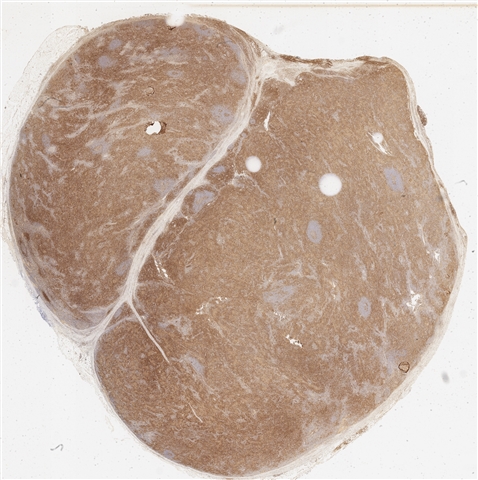

案例3 (6862)

性别:       年龄:65

患者详情: 患者3月余前在当地社区卫生服务中心体检发现血肌酐升高(109.8umo/L),无明显尿量减少,无颜面下肢浮肿无腰酸腰痛,无肉眼血尿,无关节疼痛,无皮疹红斑,开始未重枧及进一步诊治。10余天前患者到中山医院复查生化提示“肌酐200umol/L、尿素7.3mmol/L、尿酸637umol/L、白蛋白34g/L、球蛋白66g/L、蛋白电泳β15.0%、蛋白电泳Y42.6%”,同时其它检查提示“血lgG4 54.20g/L”。 CT:纵隔及双侧腋下多发肿大淋巴结,肺动脉干稍増粗,主动脉硬化,扫及双肾饱满,后腹膜发淋巴结。 PET-T:全身多区域淋巴结肿大、双侧泪腺、双侧颌下腺及胰腺体尾部饱满、双肾实质肿胀,左侧头皮局部增厚,伴FDG代谢增高,鼻咽顶后壁及前列腺腺体FDG代谢增高,上述病灶首先考虑IgG4相关性疾病所致可能,建议暖股沟淋巴结活检病理明确除外淋巴瘤。

大体所见: 结节一枚3*3*2cmA-C。

医院: 上海交通大学医学院附属仁济医院